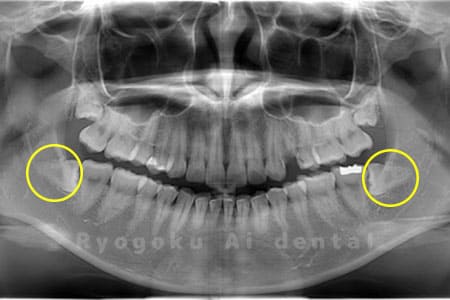

Case04

- 原因

- 上顎の親知らず、下顎の水平埋伏の親知らず

- 治療内容

- 上顎の親知らず、下顎の水平埋伏の親知らずを抜歯したケースです。

<リスク・副作用>

手術後は痛み、腫れ、痺れなどの副作用が生じる場合があります。